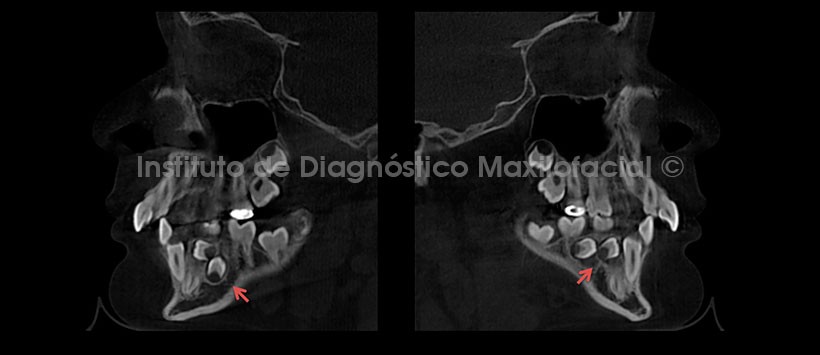

A la evaluación de la tomografía volumétrica (CBCT) en cortes axiales (Figura 2), coronales (Figura 3) y sagitales (Figura 4), se observan los folículos antes descritos en evolución intraósea, con proximidad hacia la tabla ósea lingual, sin causar alteración de las estructuras adyacentes.